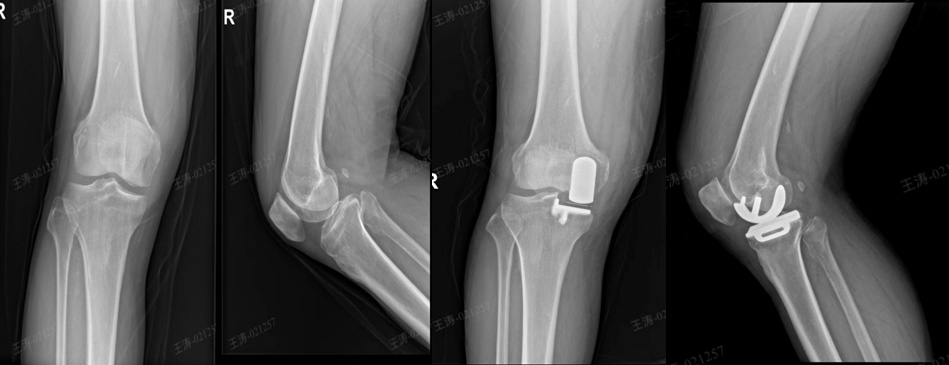

适用于仅单一间室(多为内侧)严重磨损,但前后交叉韧带、其他间室及髌股关节均功能良好的患者。技术精髓在于仅置换膝关节受损的“一半”,创伤更小、出血更少。

核心优势体现在快速康复与极致仿生,术后第二天即可下地行走,康复速度明显快于全膝置换。更重要的是,它最大限度地保留了膝关节自然的生物力学和本体感觉,患者术后常感觉“几乎忘了膝盖做过手术”,尤其能满足散步、旅游、甚至适度运动的需求。